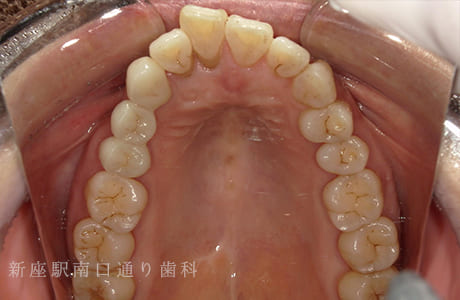

CASE.04

右上にフルジルコニアブリッジで

修復した症例

-

術前

術中

術後年

- 主訴

- 歯がないところを治したい

- 治療法

- 右上にフルジルコニアブリッジで修復

- 治療期間

- 1ヶ月半

- 費用

- ¥280,000(税込)

【リスク・副作用】

過度の咬合や衝撃で割れることがあります。治療直後は歯や歯茎に一時的な違和感や痛みが出ることがあります。